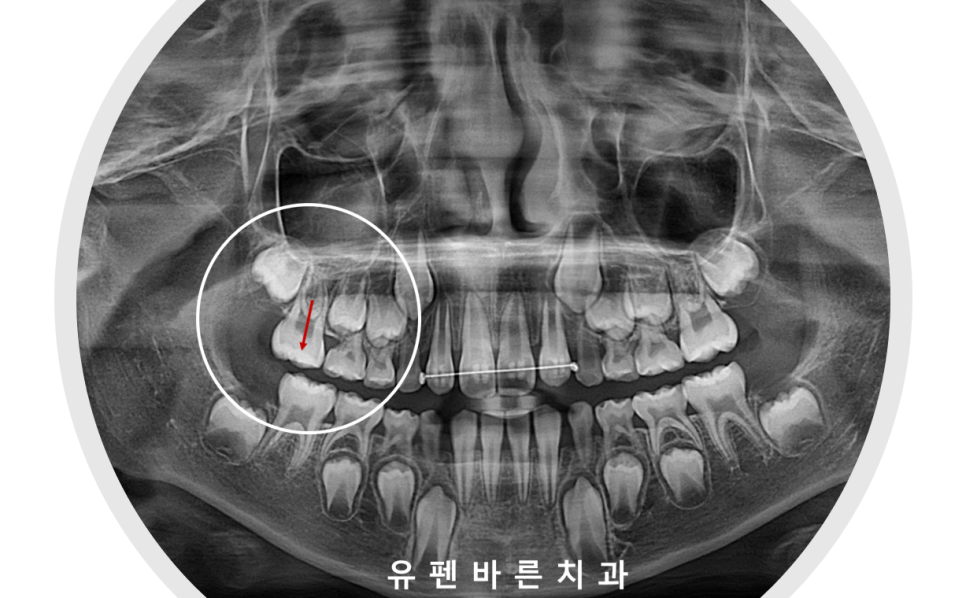

반대교합이 있는 이 6세 남아의 경우에는

양쪽 어금니에

악궁확장장치를 고정시키고

앞니 4개, 어금니 2개에만 브라켓을 붙여

교정하는 방식으로 진행 되었습니다.

또한

이 아이의 경우

오른쪽 위의 첫번째 영구치가

앞 유치에 걸려

맹출이 잘 되지 못하고 있었는데요,

halterman 이라는 장치를 통해

어금니의 올바른 맹출을

함께 유도해 주었습니다 :)